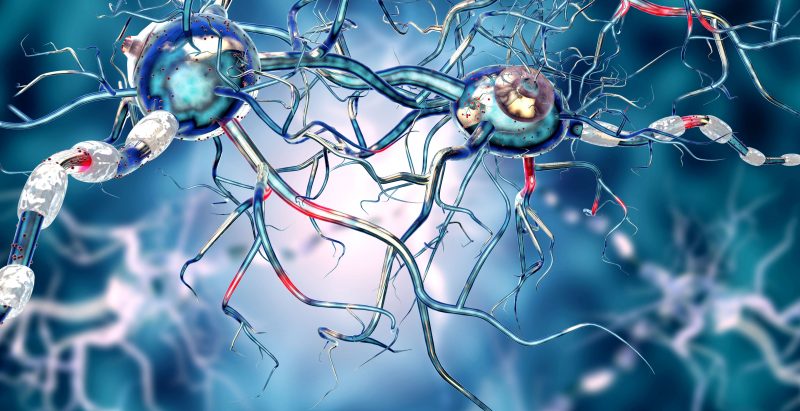

New research reveals how B cells balance mutation and clonal expansion to refine their antibodies. This discovery could lead to more targeted and effective vaccine designs for various diseases.